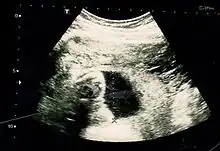

Fetus at 17 weeks

Obstetric ultrasonography is routinely used for dating the gestational age of a pregnancy from the size of the fetus, determine the number of fetuses and placentae, evaluate for an ectopic pregnancy and first trimester bleeding, the most accurate dating being in first trimester before the growth of the foetus has been significantly influenced by other factors.[22] Ultrasound is also used for detecting congenital anomalies (or other foetal anomalies) and determining the biophysical profiles (BPP), which are generally easier to detect in the second trimester when the foetal structures are larger and more developed.[23]

X-rays and computerized tomography (CT) are not used, especially in the first trimester, due to the ionizing radiation, which has teratogenic effects on the foetus.[24] No effects of magnetic resonance imaging (MRI) on the foetus have been demonstrated,[25] but this technique is too expensive for routine observation. Instead, obstetric ultrasonography is the imaging method of choice in the first trimester and throughout the pregnancy, because it emits no radiation, is portable, and allows for realtime imaging.[26]

The safety of frequent ultrasound scanning has not been confirmed. Despite this, increasing numbers of women are choosing to have additional scans for no medical purpose, such as gender scans, 3D and 4D scans.[27] A normal gestation would reveal a gestational sac, yolk sac, and fetal pole.[28]

The gestational age can be assessed by evaluating the mean gestational sac diameter (MGD) before week 6, and the crown-rump length after week 6. Multiple gestation is evaluated by the number of placentae and amniotic sacs present.[29]